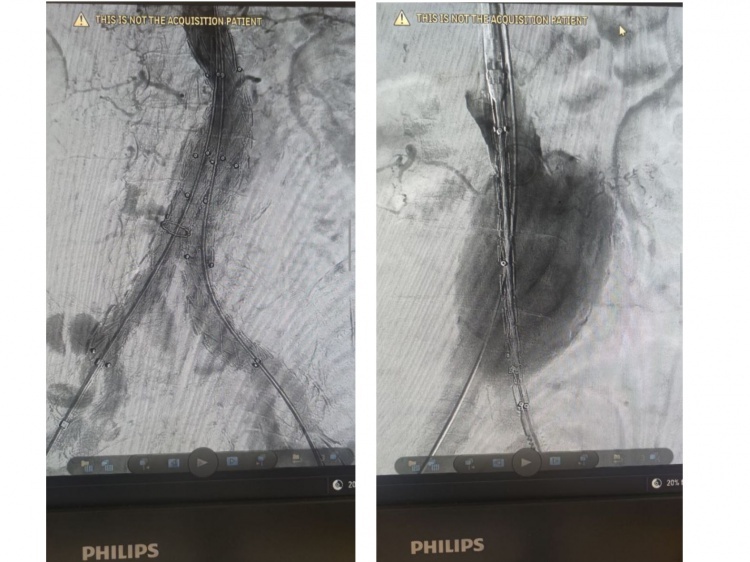

В Волгоградской областной клинической больнице № 1 успешно провели сложную и уникальную операцию. Как сообщили Волжский.ру в комитете здравоохранения, у пациента старше 70 лет имелась крупных размеров аневризма с угрозой разрыва, имелись симптомы сдавления окружающих органов и тяжелые хронические заболевания. Совокупность этих факторов делала традиционное открытое вмешательство очень рискованным. Поэтому было решено провести эндоваскулярное вмешательство и установить стент-графт для лечения аневризмы брюшной аорты.